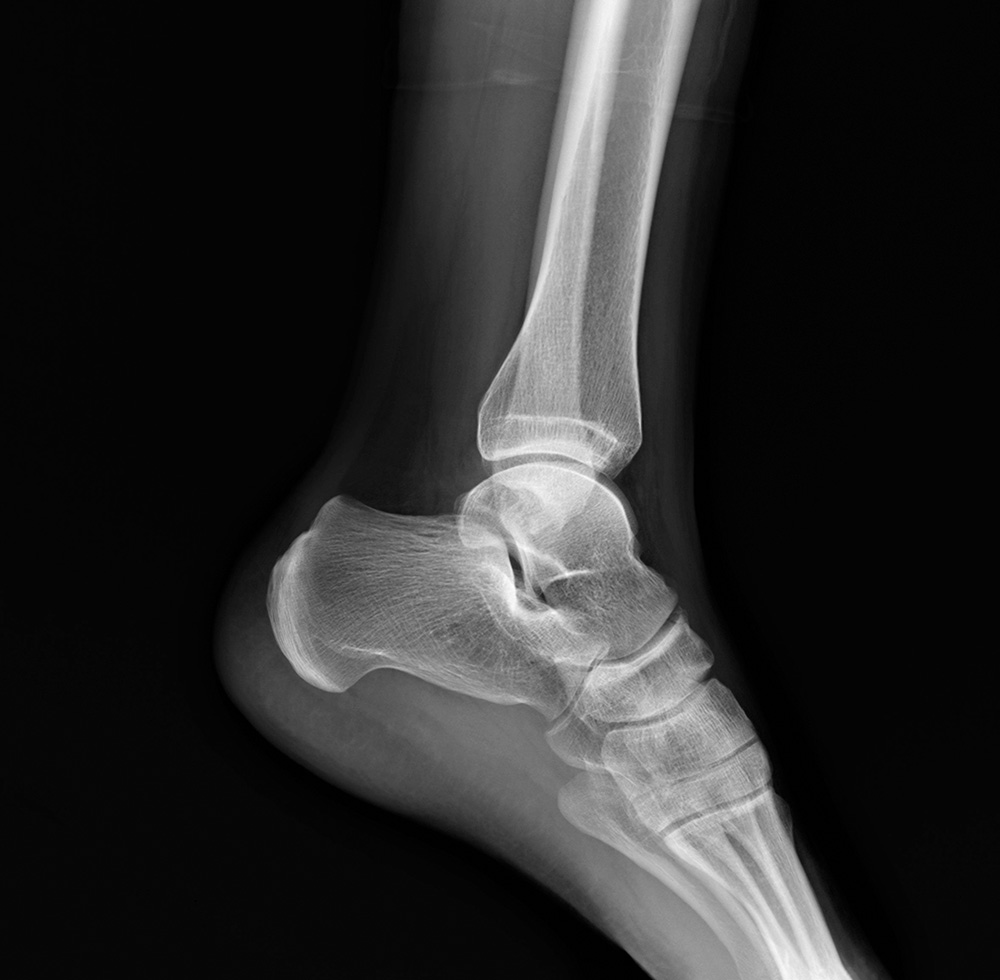

Diagnosing an ankle fracture

If a fracture is suspected, additional imaging tests may be ordered to better understand the injury:

- X-rays – The most common imaging technique, X-rays show whether the bone is broken, the number of fracture pieces, and if there is any displacement. X-rays of the leg, ankle, and foot may also be taken to check for other injuries.

- Stress Test – For certain fractures, the doctor may apply pressure to the ankle and take a special X-ray to determine if surgery is needed.

- CT scan – Provides detailed cross-sectional images of the ankle, especially useful if the fracture extends into the joint.

- MRI Scan – Produces high-resolution images of bones and soft tissues, such as ligaments, to check for associated injuries.